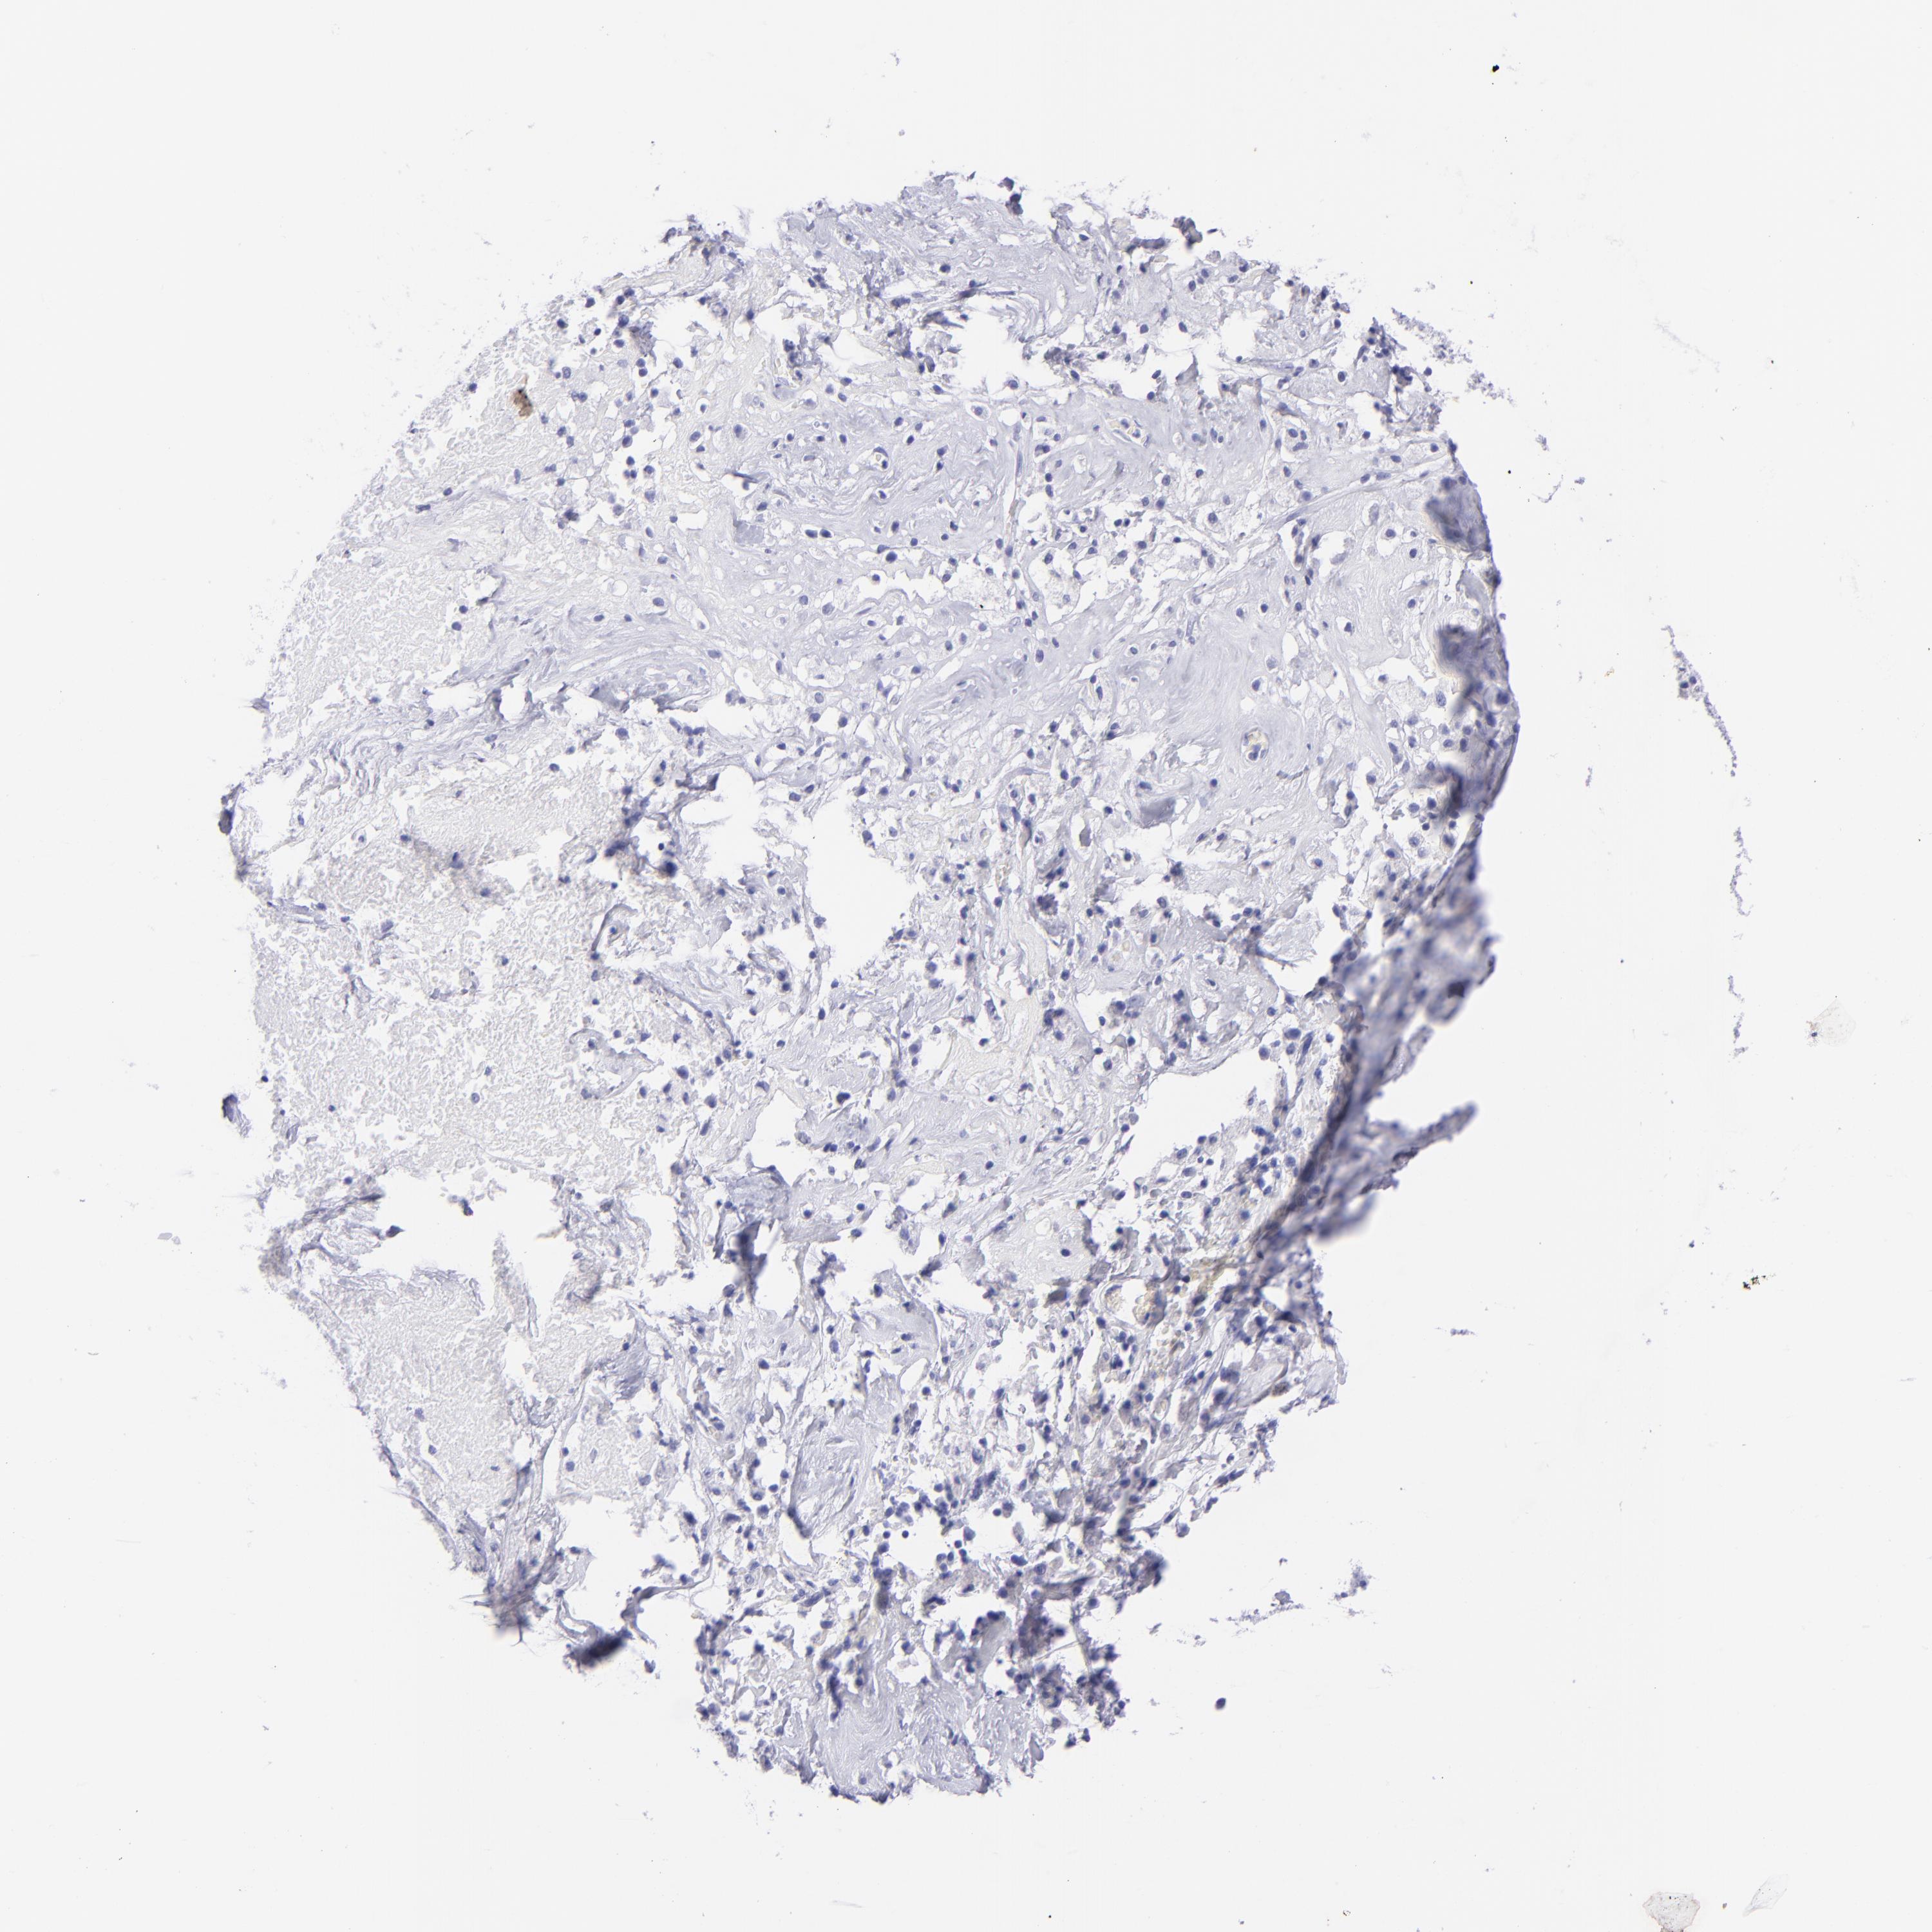

OVARIAN CANCER - Protein expressioni

A mouse-over function shows sample information and annotation data. Click on an image to view it in a full screen mode. Samples can be filtered based on level of antibody staining by selecting one or several of the following categories: high, medium, low and not detected. The assay and annotation is described here.

Note that samples used for immunohistochemistry by the Human Protein Atlas do not correspond to samples in the TCGA dataset.

Antibody stainingi

Antibody staining in the annotated cell types in the current human tissue is reported as not detected, low, medium, or high, based on conventional immunohistochemistry profiling in selected tissues. This score is based on the combination of the staining intensity and fraction of stained cells.

Each image is clickable and will lead to virtual microscopy that enables deeper exploration of all samples and also displays staining intensity scores, fraction scores and subcellular localization as well as patient and tissue information for each sample.

Antibody HPA009177

Antibody CAB002661

Cystadenocarcinoma, serous, NOS

Carcinoma, endometroid

Cystadenocarcinoma, mucinous, NOS

Carcinoma, NOS